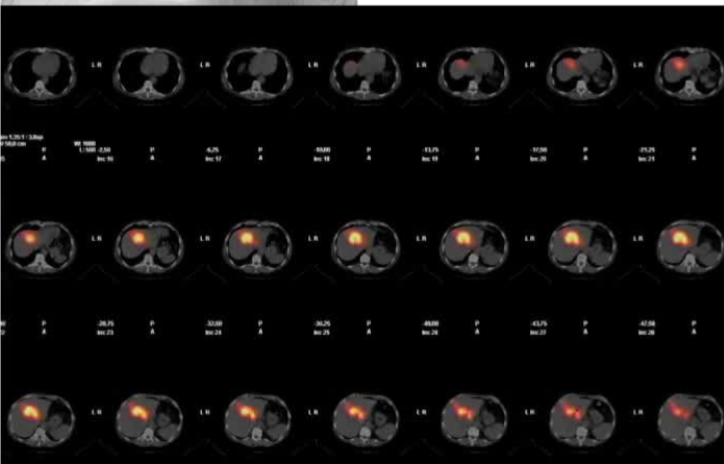

![]() ![]() 上图是一篇论文报告了一项针对不可切除肝内胆管癌(iCC)的创新性降期治疗联合肝移植的前瞻性研究。以下是该研究的核心内容总结: 研究背景

· 肝内胆管癌是一种侵袭性胆道恶性肿瘤,手术切除是唯一可能治愈的手段,但70%-80%的患者确诊时已无法切除。 研究目的 评估一项结合全身化疗(吉西他滨+顺铂)与放射性栓塞(TARE)的序贯降期方案,用于筛选适合肝移植的不可切除iCC患者,并报告前13例患者的意向性治疗结果。 研究方法

·纳入标准:单发肿块型iCC(可伴卫星灶)、血管包绕但无癌栓、无淋巴结或肝外转移、年龄18-70岁、PS 0-1。

1.4周期吉西他滨+顺铂化疗;

反应评估:采用RECIST、Choi标准及FDG-PET,并监测肿瘤标志物。 主要结果

入组情况:13例患者,中位年龄60岁,77%为女性,多数(57%)伴有代谢相关脂肪性肝病,中位肿瘤直径100mm。

o 中位从诊断到移植时间9个月,等待时间57天; ·非移植患者:中位OS从诊断起29个月,从退出起11.5个月,8例死亡(均为肿瘤进展)。 结论与讨论

· 联合化疗+TARE的降期方案可使部分不可切除iCC患者获得肝移植机会,移植后长期生存良好。 局限性

· 单中心、样本量小; 83 岁的女性,体重超标 40 毫米单发 ICC(S7-S8) 中肝静脉和右肝静脉浸润性,活检:非酒精性脂肪性肝炎(慢性肝病),马斯氏(MaS)病(30%)

考虑采用“三步策略 TARE→ PVE → Surgery”方案 剂量活性:1.56 和 3.16 GBq